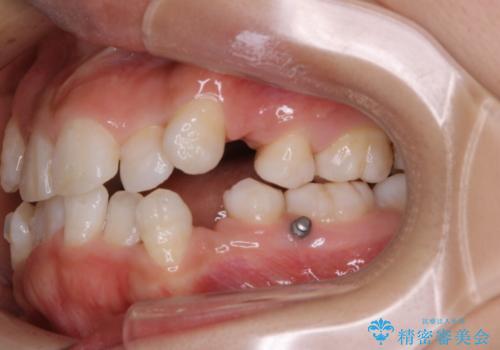

- インビザライン中に、コーヒーによる着色が気になるとのことでした。PMTC60分コースを行いました。

PMTC(保険外治療)は、毎日の歯磨きで落としきれない汚れや、コーヒ、紅茶・タバコのヤニなどの着色も除去します。目には見えない歯と歯の間・歯肉の境目・インビザライン中はアタッチメント周囲などに残っているプラーク(歯垢)もしっかり取り除きます。PMTCでは専門的な機械や材料を使用して、徹底的に汚れを除去するため、虫歯・歯周病・口臭予防などにつながります。